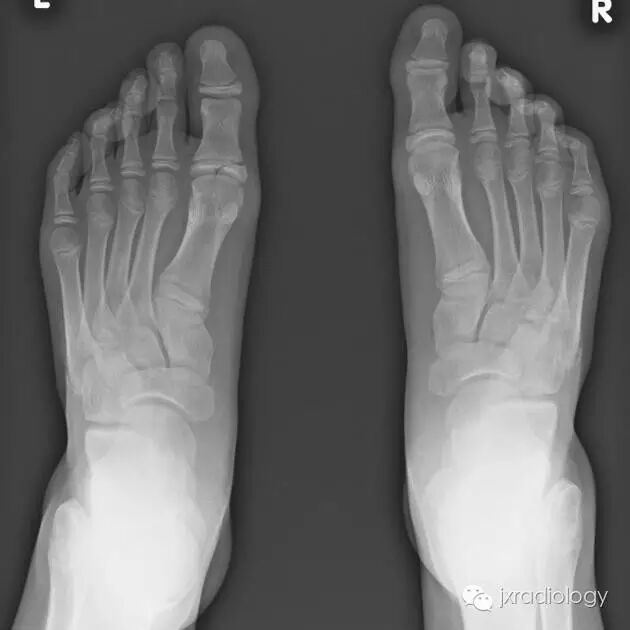

骨骺裂是一种正常变异。它可以是单侧或双侧,最常见的部位是足的第1趾近节趾骨的骨骺。

骨骺裂是骨骺的正常变体。它可以是单侧或双侧最常见的部位是足部第一近端指骨的骺前。

X线平片显示骨骺见透亮状裂隙影;透亮影的边缘是可变的,可能是锐利的或不规则的。骨骺裂可保留至生长板的融合。

X线平片将显示骨骺有透明缺损。透明度的边界是可变的,可能是尖锐的或不规则的。裂缝一直保持到生长板融合。